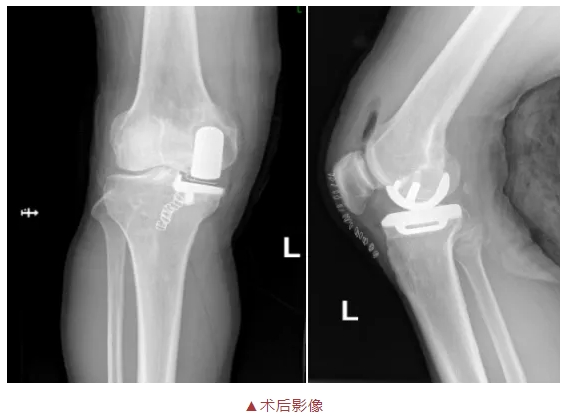

膝關(guān)節(jié)單髁置換術(shù)(unicondylar knee arthroplasty,UKA)開(kāi)始于20世紀(jì)70年代,是保膝手術(shù)治療的一種,只對(duì)磨壞的一半關(guān)節(jié)表面進(jìn)行置換。單髁置換手術(shù)類似于補(bǔ)車胎,就是將表面磨壞的骨頭和軟骨用人工表面關(guān)節(jié)進(jìn)行修補(bǔ),以達(dá)到精準(zhǔn)治療,微創(chuàng)治療的目的。

良好的效果,取決于準(zhǔn)確的適應(yīng)癥選擇,精湛的手術(shù)技術(shù)和個(gè)體化的圍手術(shù)期管理。單髁膝關(guān)節(jié)置換術(shù)的開(kāi)展標(biāo)志著醫(yī)院骨外一科在關(guān)節(jié)置換領(lǐng)域向微創(chuàng)化、精準(zhǔn)化方向再進(jìn)一步,在保證患者安全的基礎(chǔ)上,改善患者治療體驗(yàn),助力患者安全、平穩(wěn)、舒適地度過(guò)圍手術(shù)期和功能康復(fù)期。